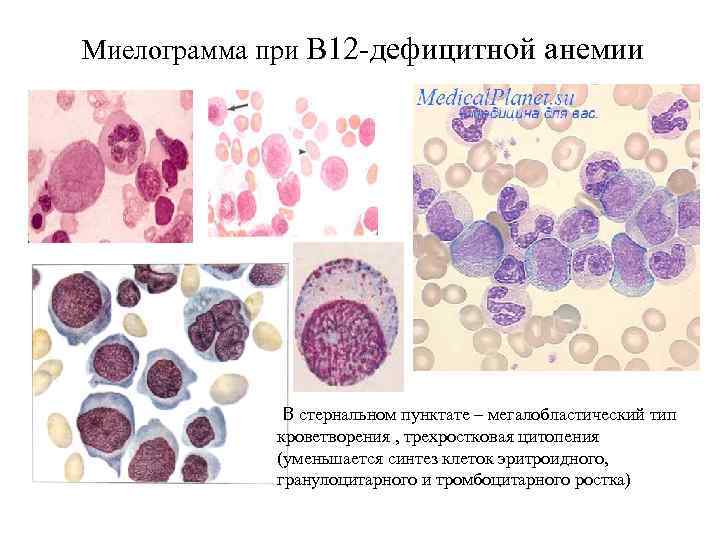

Миелограмма при В 12 -дефицитной анемии В стернальном пунктате – мегалобластический тип кроветворения , трехростковая цитопения (уменьшается синтез клеток эритроидного, гранулоцитарного и тромбоцитарного ростка)